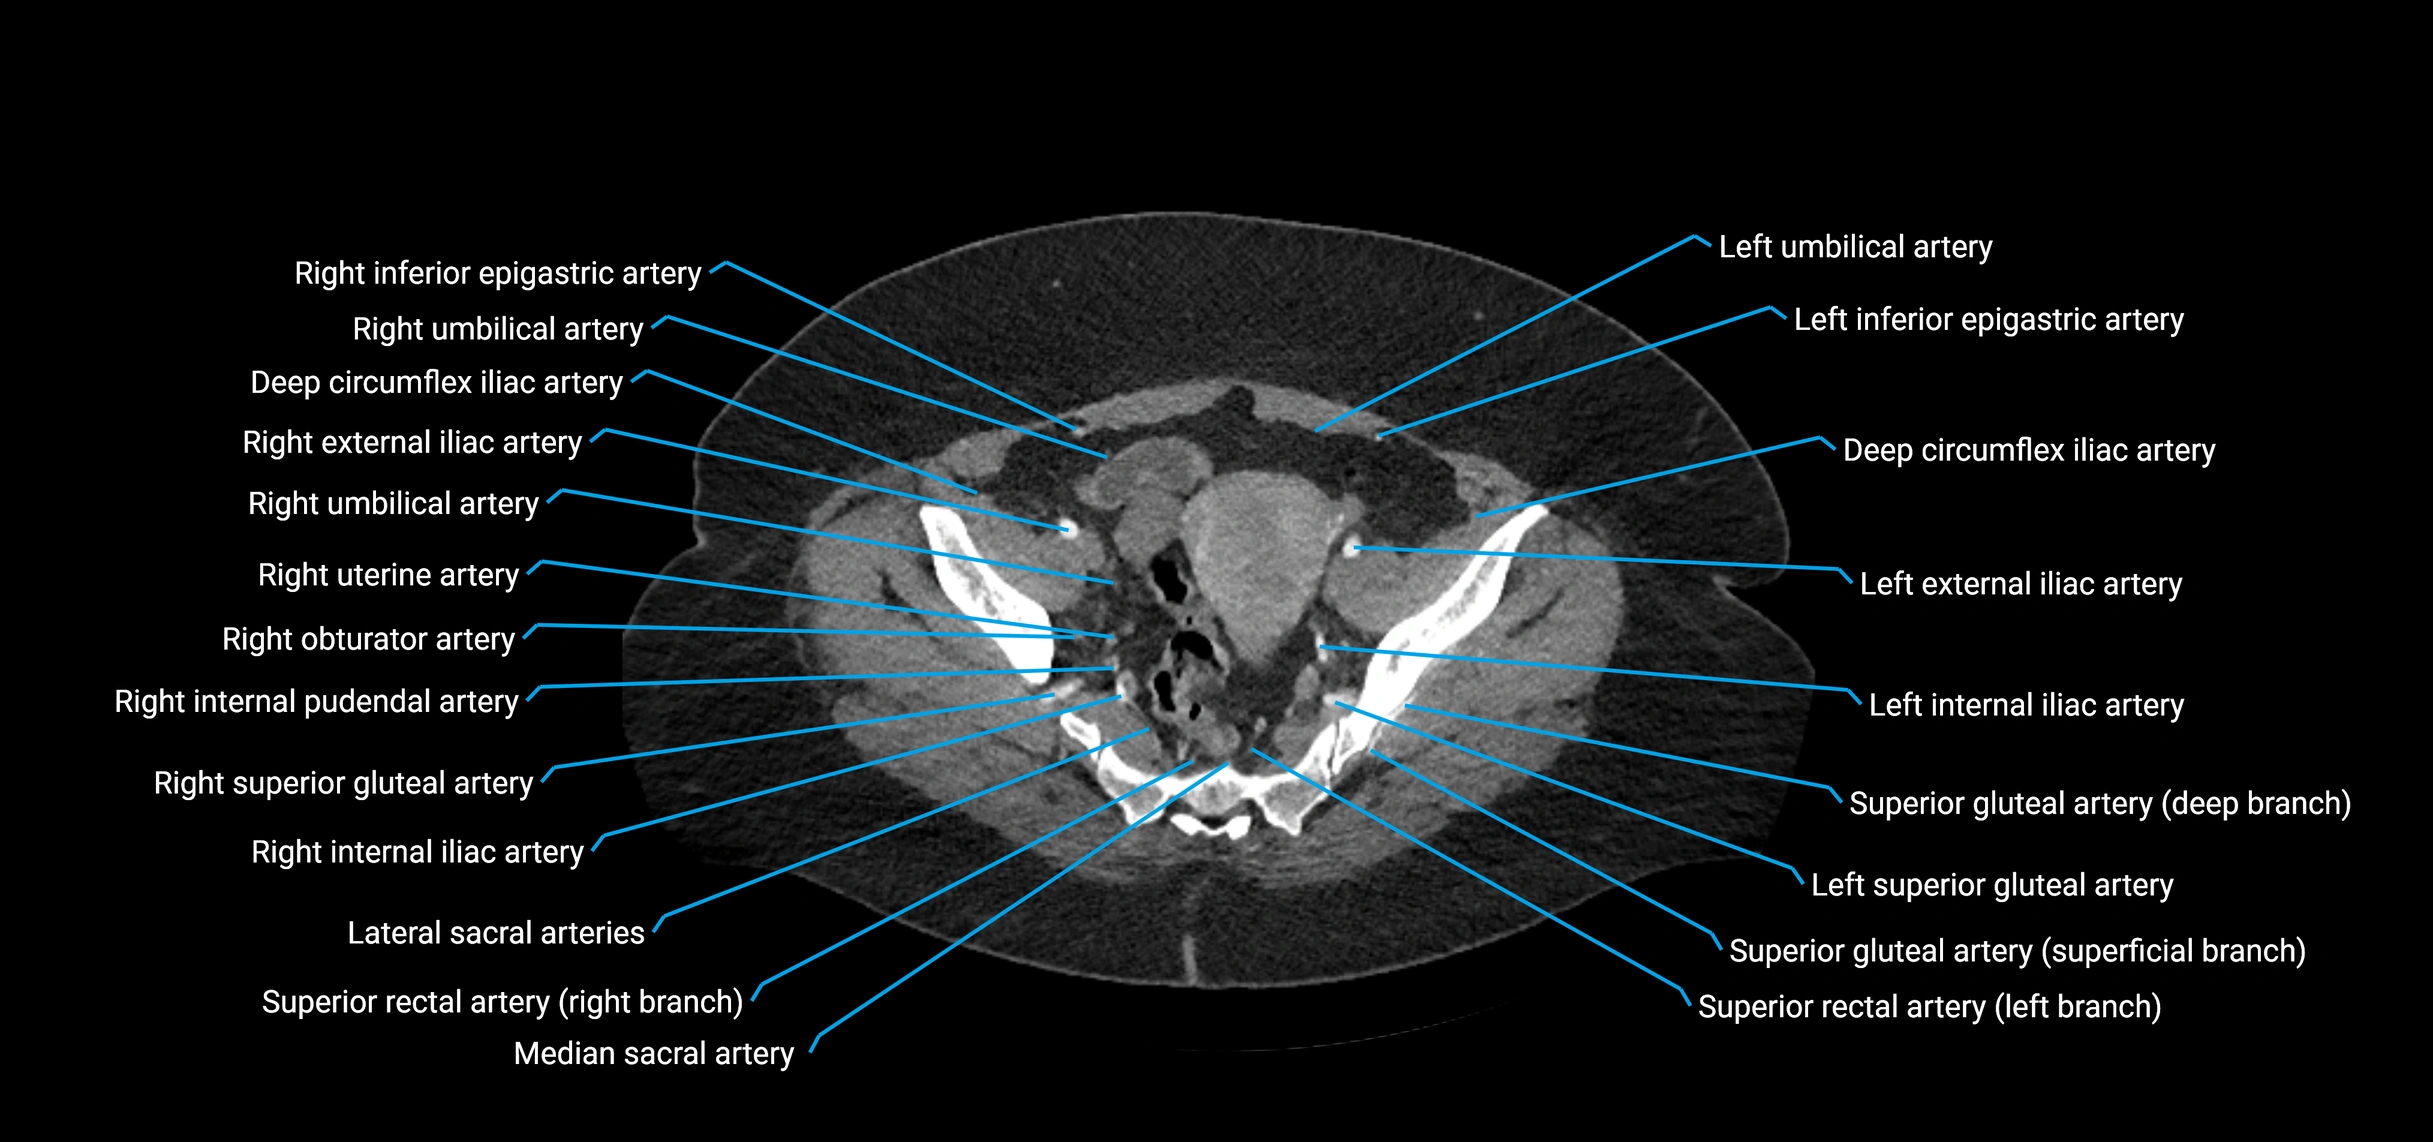

CT Appearance

Non-contrast CT:

• Appears as a tubular soft tissue structure anterior to vertebral bodies

• Calcified atherosclerotic plaques appear as hyperdense foci along the wall

• Useful for screening abdominal aortic aneurysm (AAA) size and mural calcification

Contrast-enhanced CT (CTA):

• Gold standard for abdominal aortic imaging

• Provides excellent detail of lumen, wall, aneurysm, thrombus, and branch vessels

• Multiplanar and 3D reconstructions help in aneurysm measurement, stent graft planning, and dissection evaluation

• Detects acute rupture, traumatic injury, or occlusion with high sensitivity

CT images

image